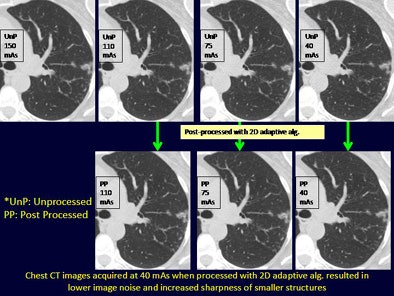

- Chest mAs settings: 150, 100, 75

Regardless of radiation dose, postprocessing with image filters improved subjective noise for both chest and abdominal CT and helped lower CT radiation dose levels for the chest by up to 40 mAs and for the abdominal CT by up to 100 mAs, Singh said.

The quantitative average image noise in postprocessed low-dose chest and abdominal CT images was significantly lower than in low-dose unprocessed images (p < 0.001).

Although the diagnostic confidence of low-dose postprocessed images was high at 40 mAs for chest CT, postprocessed abdominal CT images were rated as "fully confident" only at 100 mAs and not 50 mAs, the group reported.

Adaptive filtering decreases image noise and enhances the diagnostic confidence of low-dose chest (40 mAs) and abdominal (100 mAs) CT exams, they concluded.

"Using the filters, we can reduce the radiation dose by 75% in the chest and by 50% in the abdomen," Singh said. "They can be used on any scanner."